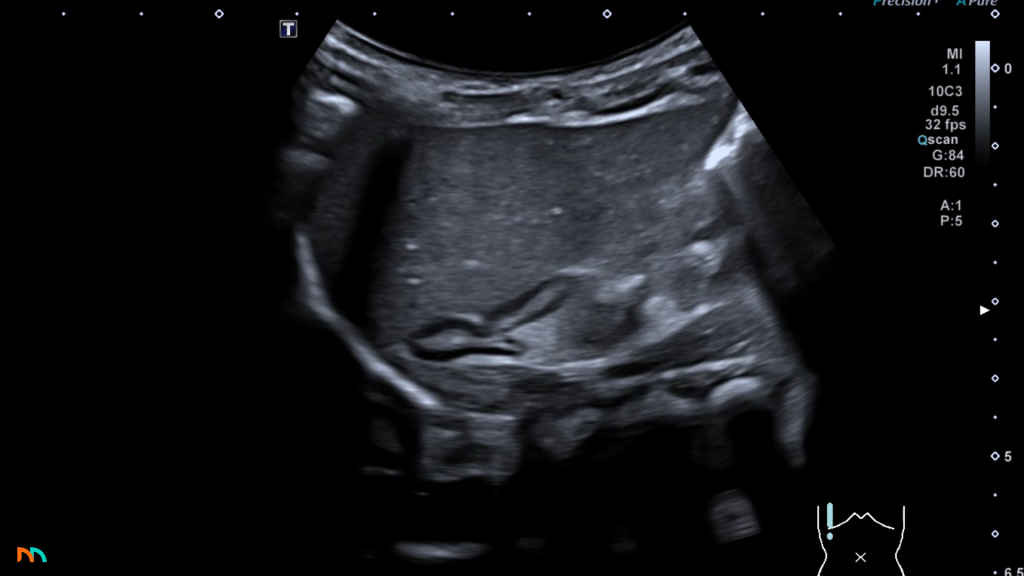

U noworodków, niemowląt i małych dzieci sytuacja jest inna. Nadnercza u tej grupy pacjentów są dużo większe w porównaniu do reszty ciała, dlatego są dużo lepiej widoczne. Bywa, że możemy, poza zarysami nadnerczy, u najmłodszych dzieci dostrzec nawet bardzo charakterystyczną, warstwową echostrukturę z wyraźnym podziałem na korę i rdzeń.